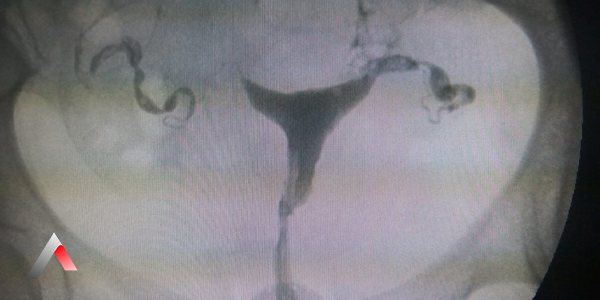

Rahim filmi veya Histerosalpingografi (HSG), rahim ve fallop tüplerinin röntgen görüntülerini elde etmek için kullanılan bir tanı yöntemidir. İşlem sırasında, rahim ağzından içeri ince bir tüp (kateter) yerleştirilir ve rahim içine özel bir boya (kontrast madde) enjekte edilir. Bu boya, rahim ve fallop tüplerinin röntgen filminde görünür hale gelmesini sağlar.

HSG işlemi sırasında, rahim ağzından içeri ince bir kateter yerleştirilir ve bu kateter aracılığıyla rahim içine iyotlu bir kontrast madde enjekte edilir. Kontrast madde, rahim ve fallop tüplerini doldururken, röntgen cihazı ile bir dizi görüntü alınır. Bu görüntüler, radyolog tarafından incelenerek rahim ve tüplerin şekli, boyutu ve açıklığı değerlendirilir.